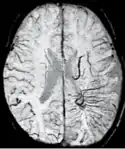

Sturge-Weber disease

An SWI venogram of a neonate with Sturge-Weber syndrome who did not display neurological symptoms is shown to the right. The initial conventional MR imaging methods did not demonstrate any abnormality. The abnormal venous vasculature in the left occipital lobe extending between the posterior horn of the ventricle and the cortical surface is clearly visible in the venogram. Due to the high resolution even collaterals can be resolved.